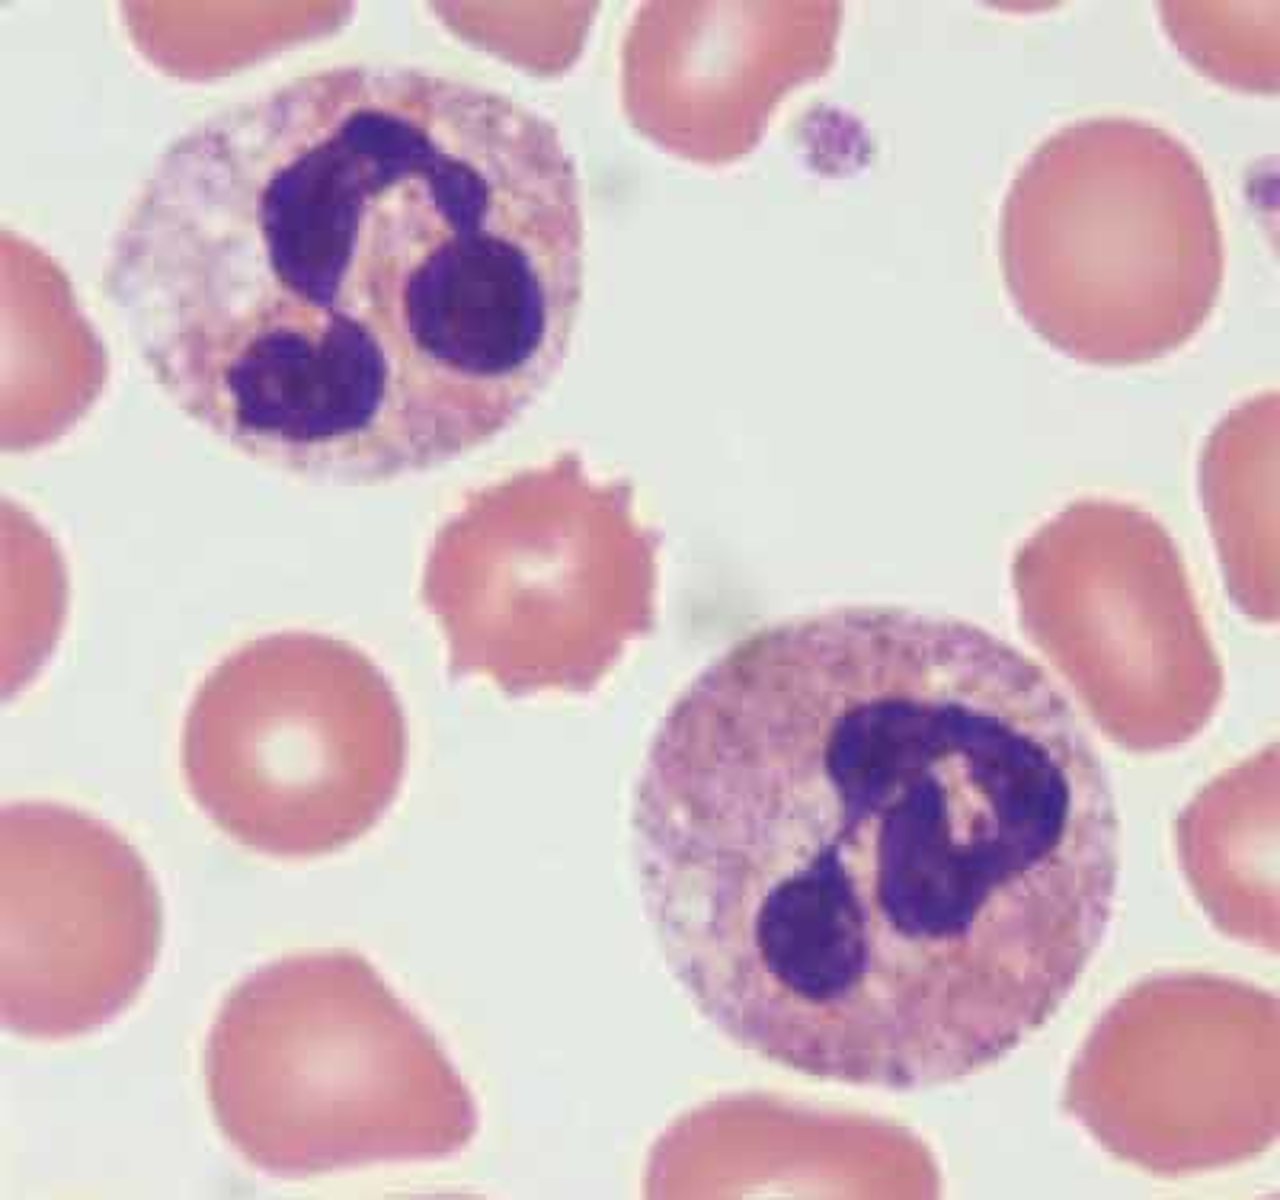

monocyte

MAMMAL

indented nucleus, basophilic cytoplasm

band neutrophils

MAMMAL

incomplete segmentation of nucleus (c-shape)

- pale-blue/purple-dark cytoplasm

hyper-segmented neutrophils

MAMMAL

"old cell"

5+ lobes

toxic neutrophils

MAMMAL

1. increase basophilia in cytoplasm

2. dohle bodies

3. vacuolated/foamy cytoplasm

4. +/- increase in cell size

dohle bodies

MAMMAL